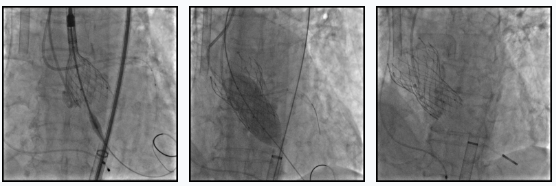

手术过程同样险象环生。使用23 mm球囊对主动脉瓣扩张时发现,冠脉开口受压可能性较大,刘巍主任立即决定使用guidezilla及球囊进行冠状动脉保护。在助手韩昊副主任医师,兰永昊主治医师等通力配合下,瓣膜被精准定位。孙华毅主任医师则承担了起搏器保驾工作。赵兴山副院长,王继红副主任也全程督战和参与抢救。正是在各位专家的悉心指导及整个团队的精准配合下,并经马旃副主任医师术中超声的反复评估确认,瓣膜被顺利释放。术后造影提示瓣膜固定良好,膨胀效果良好释放至工作位置,经造影确认瓣膜工作状态良好,瓣膜狭窄得到明显缓解。

患者术后即拔出ECMO

瓣膜释放后有少量瓣周漏,进行后扩张后,支架位置良好,工作良好